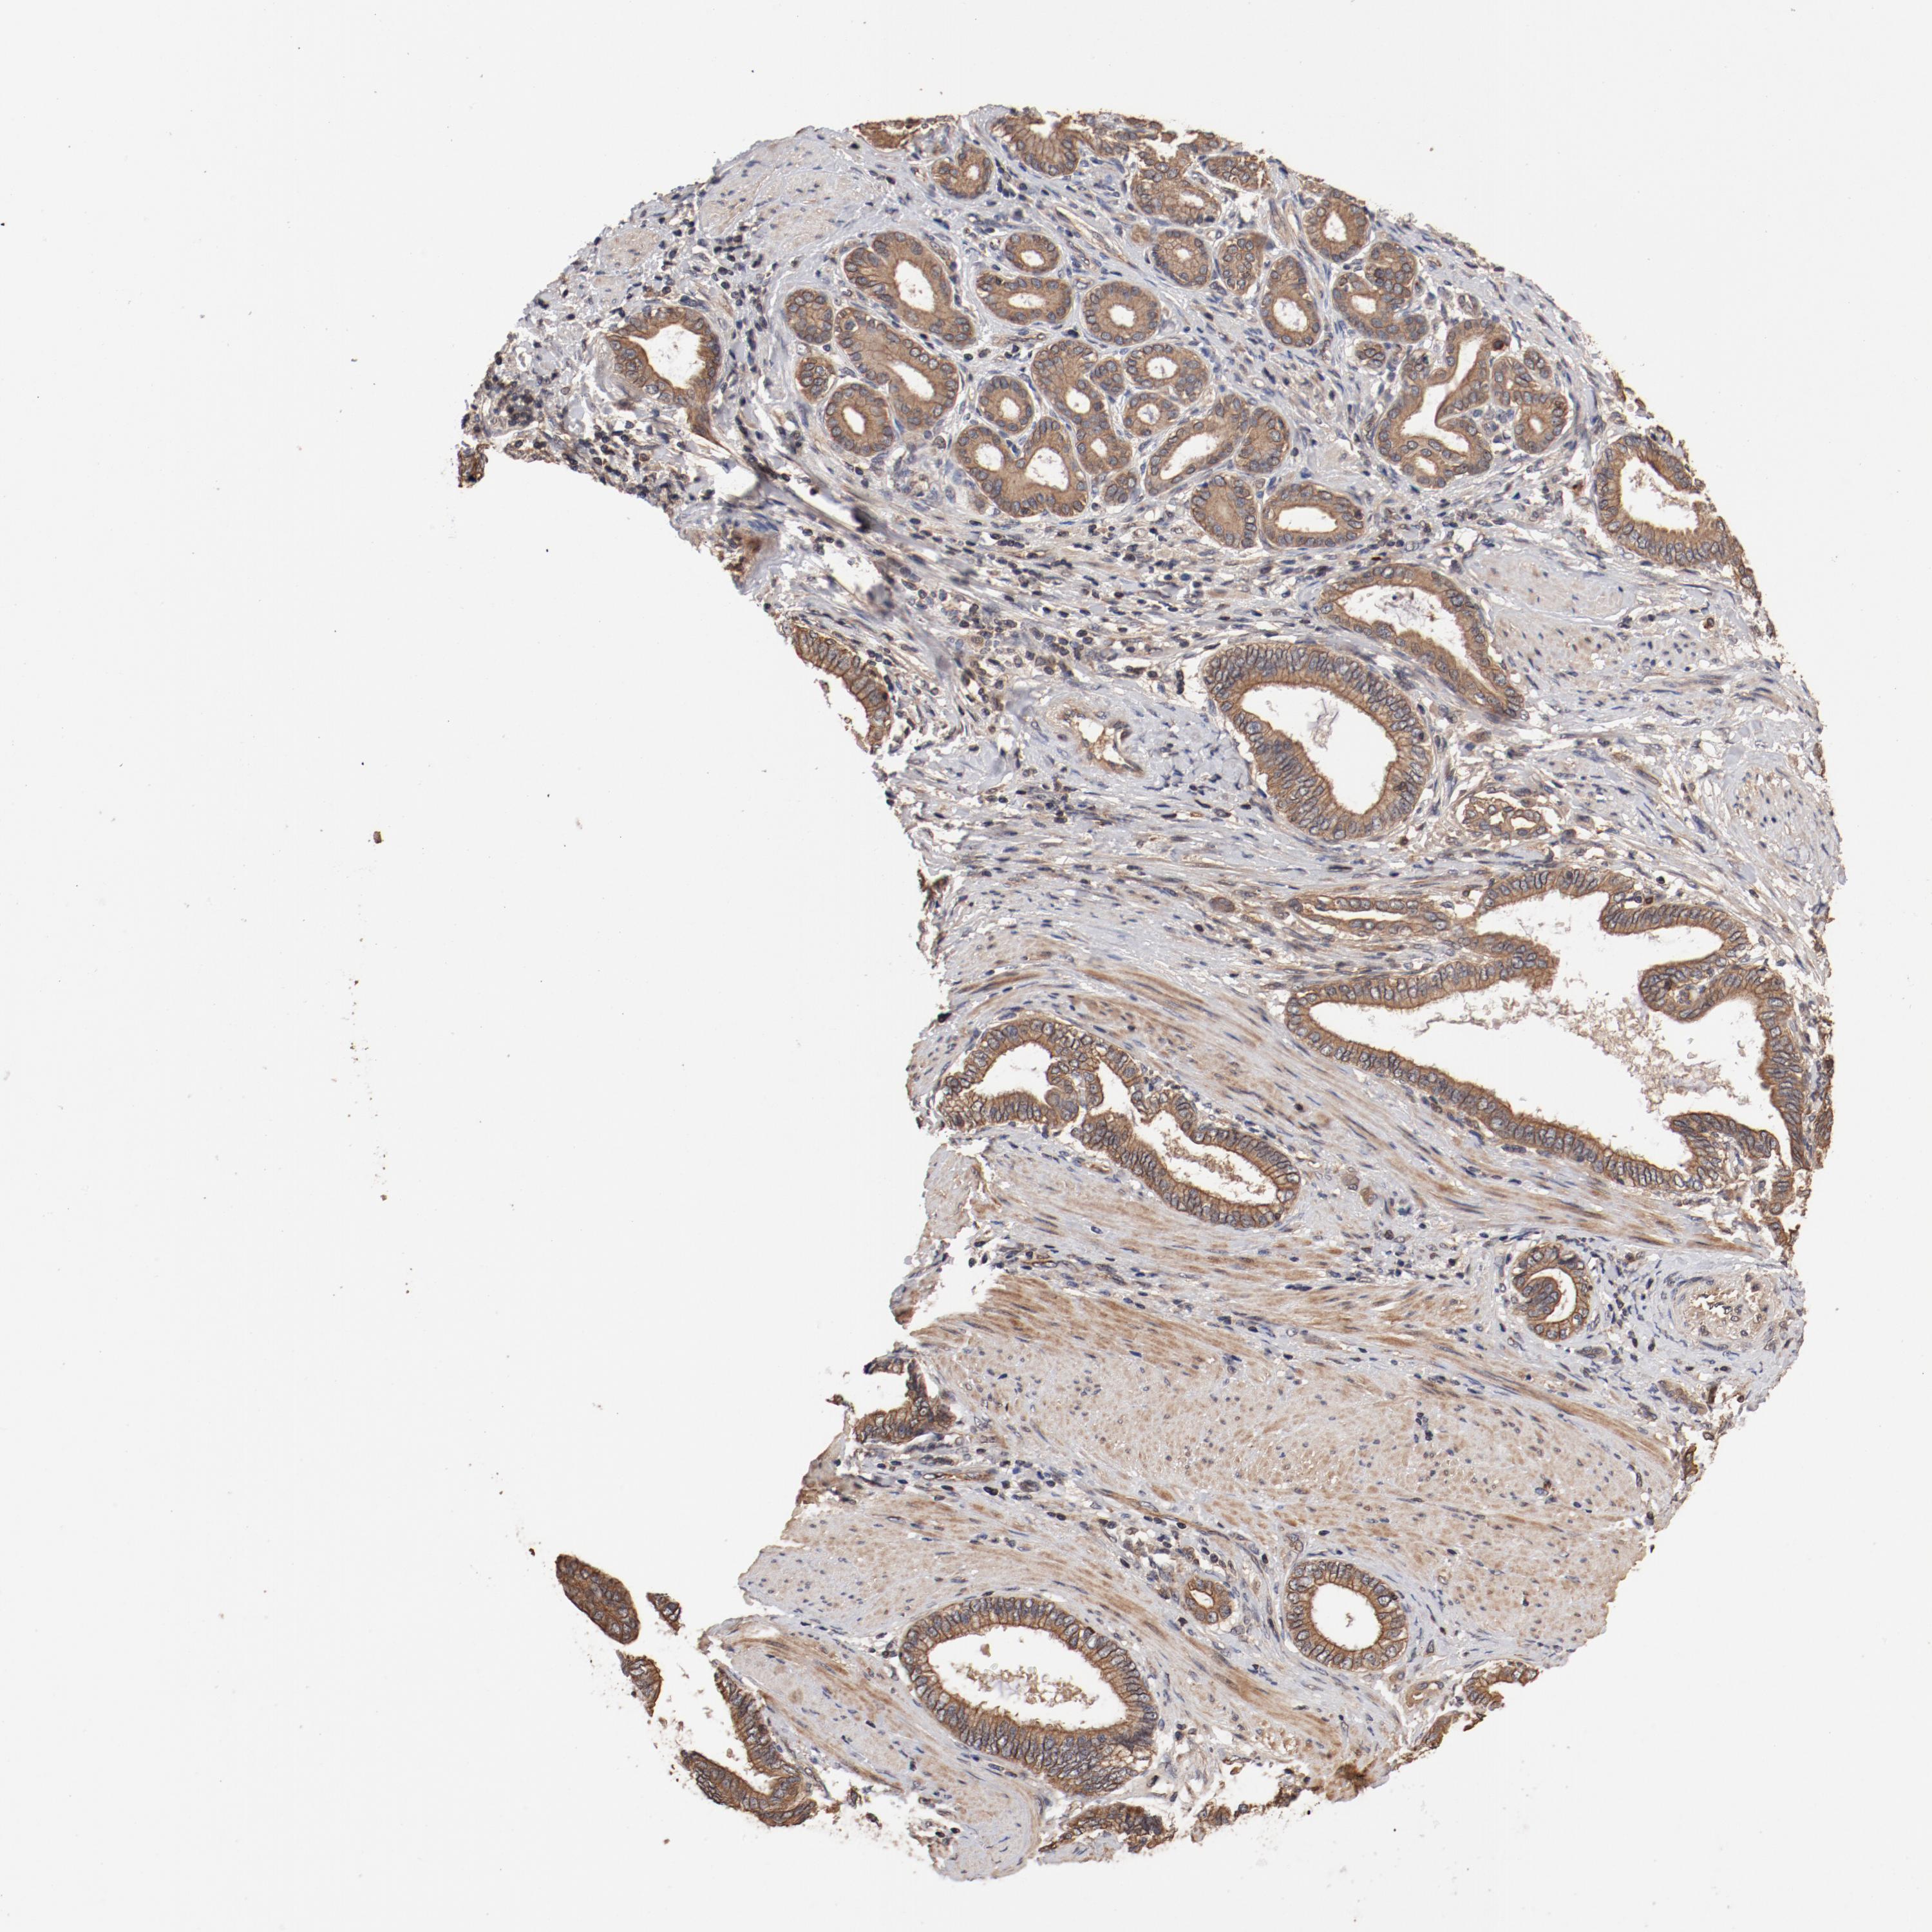

PANCREATIC CANCER - Protein expressioni

A mouse-over function shows sample information and annotation data. Click on an image to view it in a full screen mode. Samples can be filtered based on level of antibody staining by selecting one or several of the following categories: high, medium, low and not detected. The assay and annotation is described here.

Note that samples used for immunohistochemistry by the Human Protein Atlas do not correspond to samples in the TCGA dataset.

Antibody stainingi

Antibody staining in the annotated cell types in the current human tissue is reported as not detected, low, medium, or high, based on conventional immunohistochemistry profiling in selected tissues. This score is based on the combination of the staining intensity and fraction of stained cells.

Each image is clickable and will lead to virtual microscopy that enables deeper exploration of all samples and also displays staining intensity scores, fraction scores and subcellular localization as well as patient and tissue information for each sample.

Antibody HPA003934

Staining

High

Medium

Low

Not detected

Intensity

Strong

Moderate

Weak

Negative

Quantity

>75%

75%-25%

<25%

None

Location

Nuclear

Cytoplasmic/membranous

Cytoplasmic/membranous,nuclear

Adenocarcinoma, NOS

Adenocarcinoma, metastatic, NOS